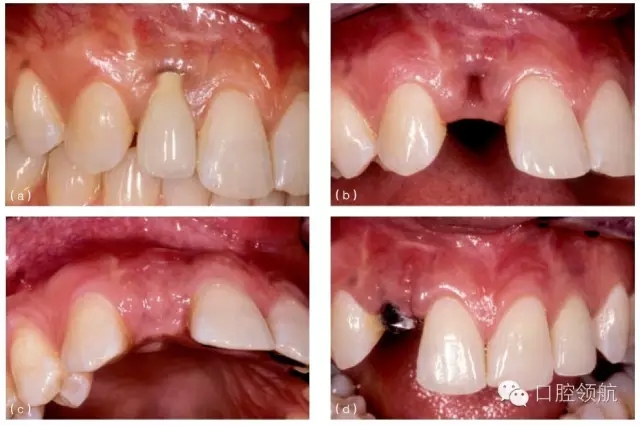

值得注意的是,種植體不能過(guò)于偏向唇側(cè),因?yàn)檫@將影響唇側(cè)黏膜的最終位置。關(guān)鍵因素是基臺(tái)唇側(cè)位置的復(fù)雜性,與鄰牙齦緣水平的唇側(cè)牙弓曲度有關(guān)??偟脑瓌t是,種植體基臺(tái)唇側(cè)最突點(diǎn)與理想牙弓曲線之間至少保留1mm的距離。由于多數(shù)基臺(tái)連接到種植體上其唇側(cè)會(huì)向外擴(kuò)展0.5mm,種植體應(yīng)放在距離牙弓曲線唇側(cè)1.5mm的位置(圖8.24)。種植體唇向的軸向植入位置不佳只會(huì)使問(wèn)題更嚴(yán)重。所以,種植體唇腭向和軸向的植入位置不佳時(shí),軟組織移植治療黏膜退縮的效果是有限的。若植入位置不佳嚴(yán)重,軟組織移植也不能挽救組織退縮(圖8.25a~i)。

圖8.25 (a)右上頜側(cè)切牙(7號(hào)位點(diǎn))種植體唇側(cè)黏膜退縮。種植體有唇側(cè)植入位置不佳。(b)拆下冠和基臺(tái)并以暫時(shí)的局部義齒修復(fù)后的臨床情況。局部義齒選取正確的冠長(zhǎng)度,顯示出軟組織垂直向缺損。(c) 牙合面觀:拆下冠和基臺(tái),安裝愈合基臺(tái)。清楚可見(jiàn)種植體唇側(cè)植入位置不佳。(d)做頰側(cè)全厚瓣翻瓣,可見(jiàn)牙槽嵴骨水平與種植體相對(duì)關(guān)系算是常規(guī)位置。(e)從腭側(cè)獲取結(jié)締組織瓣,覆蓋種植體唇側(cè)與牙合面。(f)唇面觀:瓣關(guān)閉縫合后,暫時(shí)局部義齒修復(fù)。(g)術(shù)后2個(gè)月,結(jié)締組織移植瓣已完全與周圍組織融合,種植體完全覆蓋。(h)牙槽嵴頂做小切口暴露種植體頂端,安裝一個(gè)選磨過(guò)的愈合基臺(tái)。(i)種植體粘結(jié)暫時(shí)冠。原來(lái)退縮的程度有所減小,但是完全恢復(fù)軟組織的高度沒(méi)有實(shí)現(xiàn)。種植體唇側(cè)植入位置不佳時(shí),恢復(fù)的軟組織垂直高度有限。